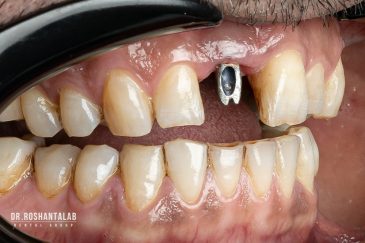

🔸 کاشت ایمپلنت دندان بدون درد

🔸کاشت ایمپلنت فلپ لس یا بدون جراحی و بدون بخیه زیر سه دقیقه

🔸 کاشت دندان یک روزه ( کشیدن و کاشت همزمان )

🔸 ایمپلنت دیجیتال و ساخت روکش دیجیتال

تجربه کاشت دندان دیجیتال و بدون درد در ۳ دقیقه! استفاده از برترین برندها زیر نظر جراح، با هزینه مناسب و خدمات کامل از کاشت دندان تا روکشارتودنسی دندان